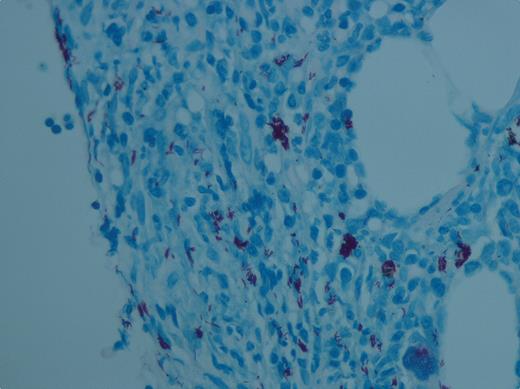

A tentative diagnosis of HIV–immune thrombocytopenic purpura (ITP) was made. She was treated with antiretroviral medications, IVIG, and subsequently with steroids for 4 weeks without improvement. Rituximab was deemed unsafe because of her immunosuppressed status. After 6 weeks of platelet unresponsiveness, a bone marrow examination was performed. The aspirate was dry. The core biopsy showed a hypercellular marrow with a heavy infiltrate of Mycobacterium avium intracellulare infection (ZN stain in figure). She was started on 4-drug antituberculosis treatment, and 2 weeks later her platelet count was 30 × 109/L. The platelet count steadily rose to 150 × 109/L by day 20 and was maintained thereafter.

This case highlights the value of performing a bone marrow examination in a patient with presumed HIV-ITP who was poorly responsive to antiretroviral medications and conventional treatment for immune thrombocytopenia. A secondary opportunistic infection was found by the bone marrow examination and the thrombocytopenia became responsive to therapy for atypical mycobacteria.